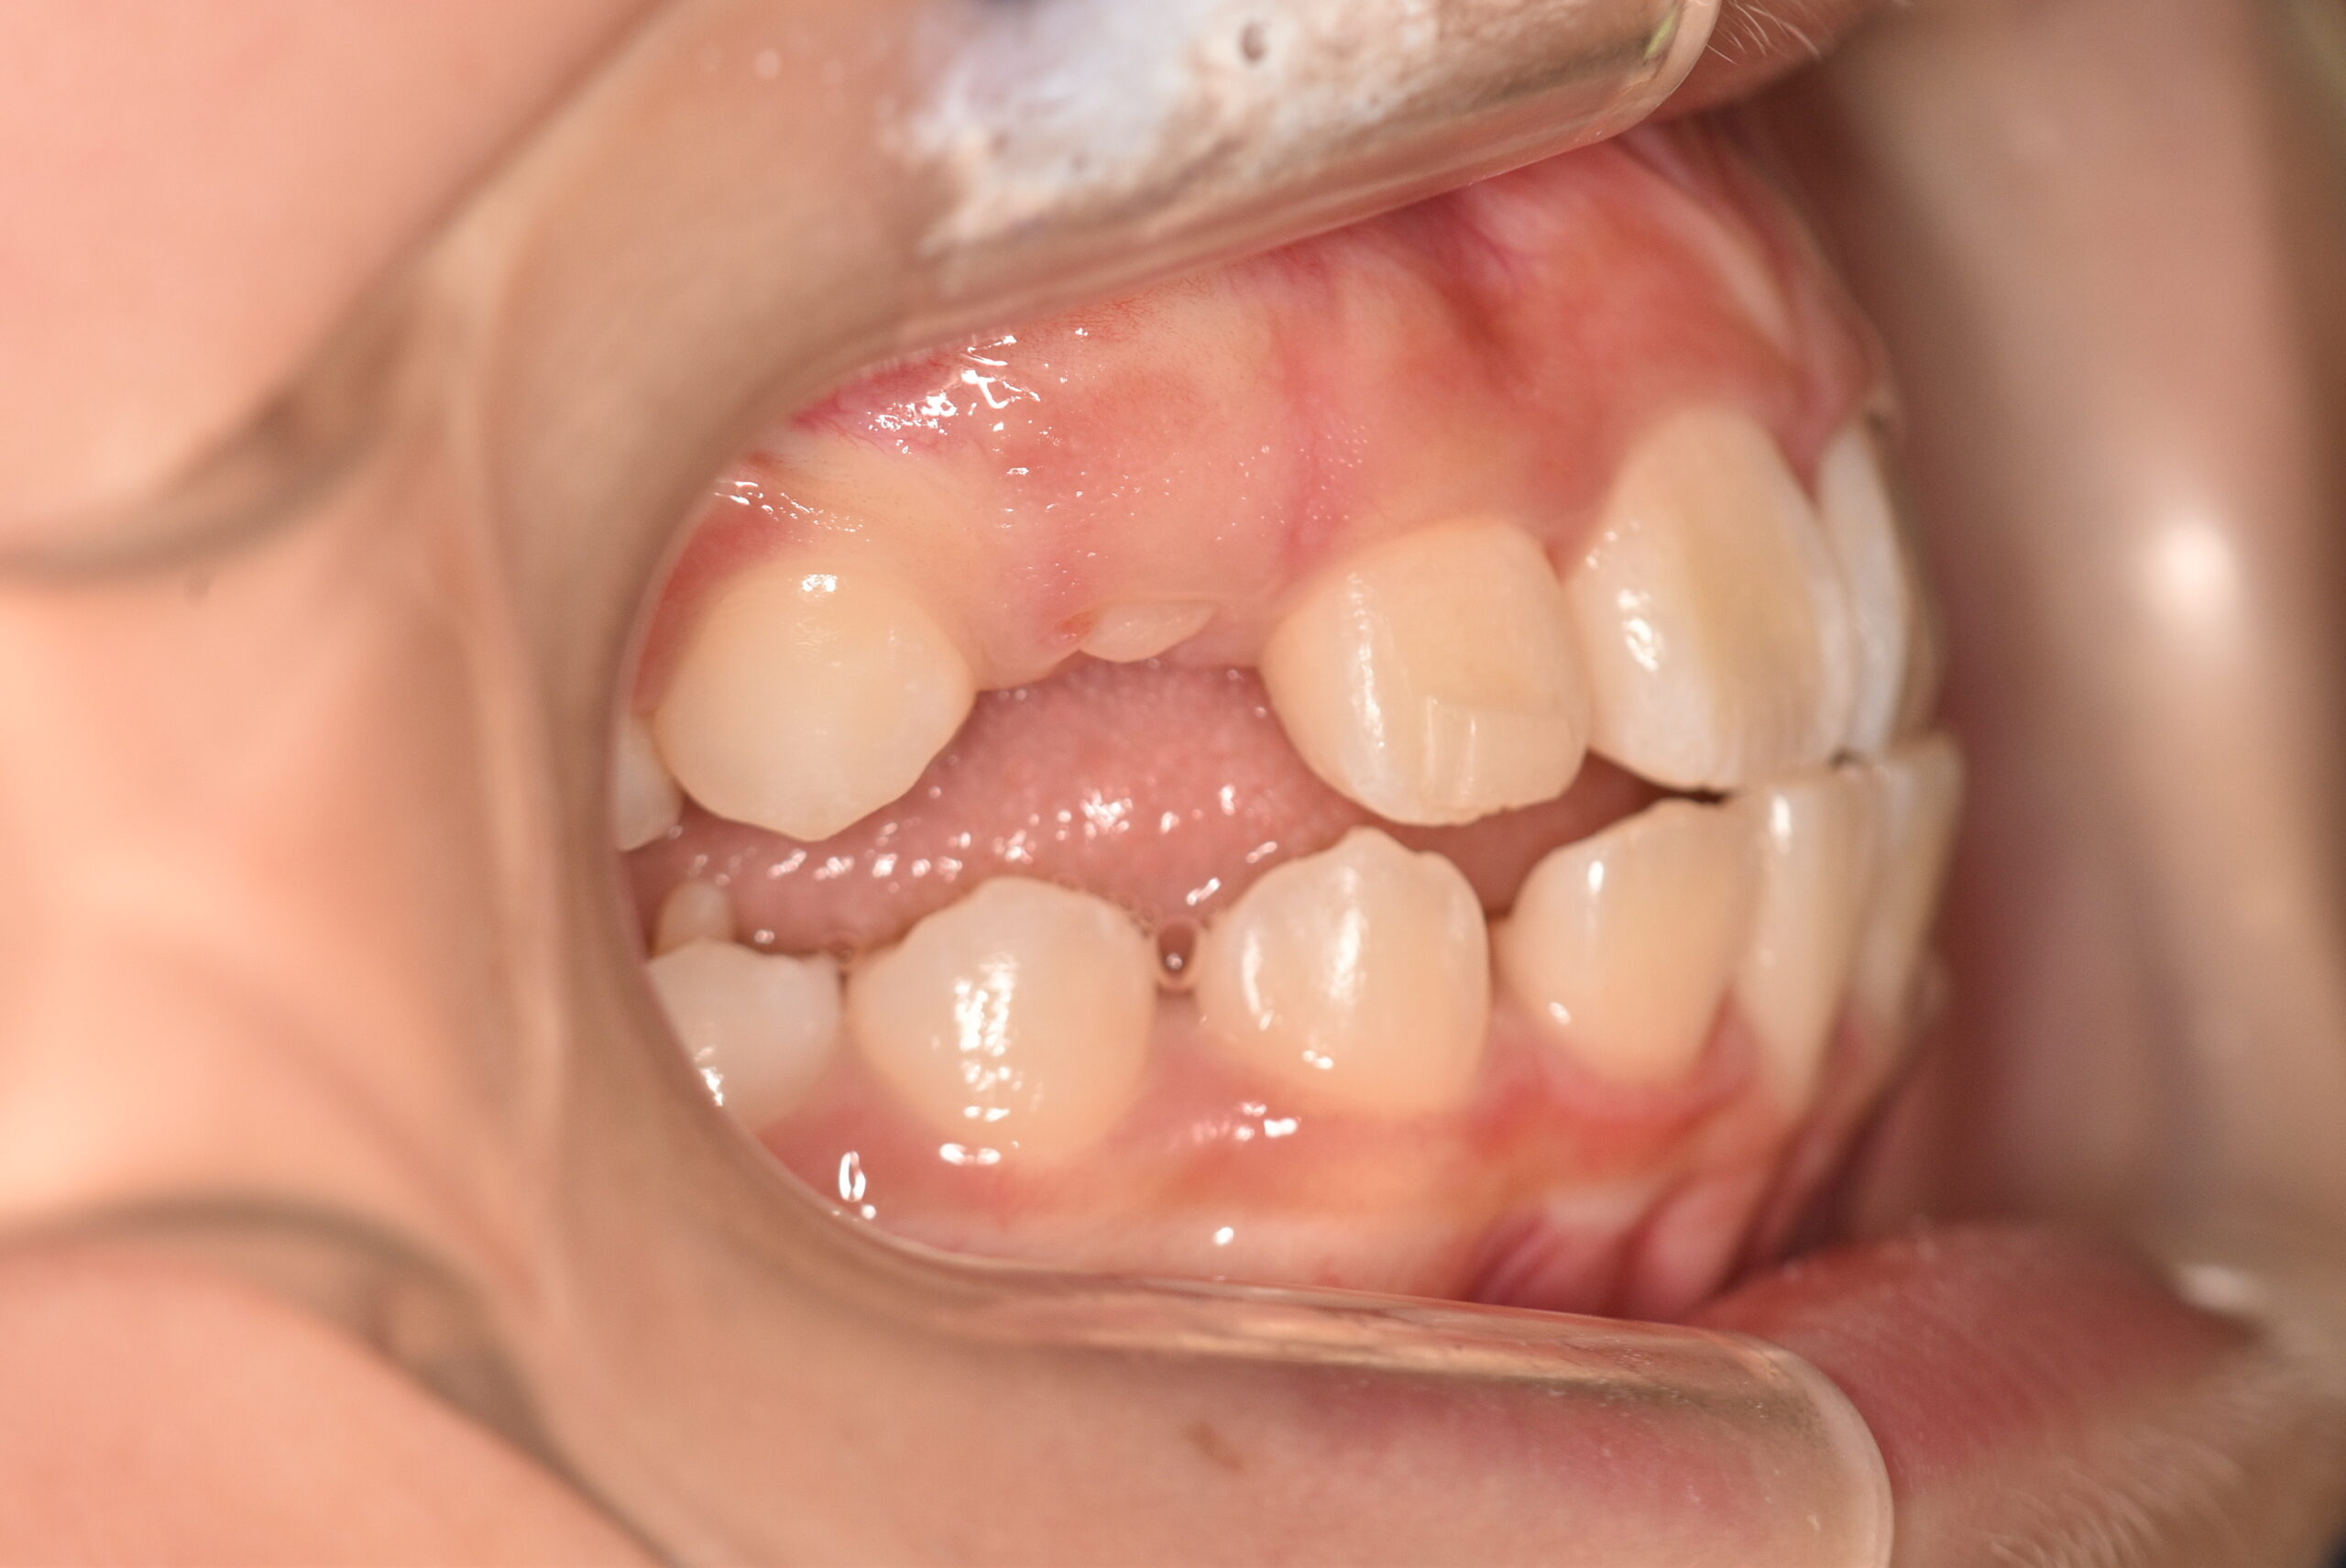

| 治療内容の詳細 | 初診時7歳の女児で、歯のがたつきを気にされ来院されました。 検査の結果、前歯部叢生を伴うアングルⅡ級不正咬合と診断しました。 治療としてはマウスピース矯正(インビザラインファースト)で配列を行い、上下顎の側方拡大と萌出スペースを確保しました。 治療期間は、1年でした。 今後、側方歯生え変わりまで経過観察を行います。 |